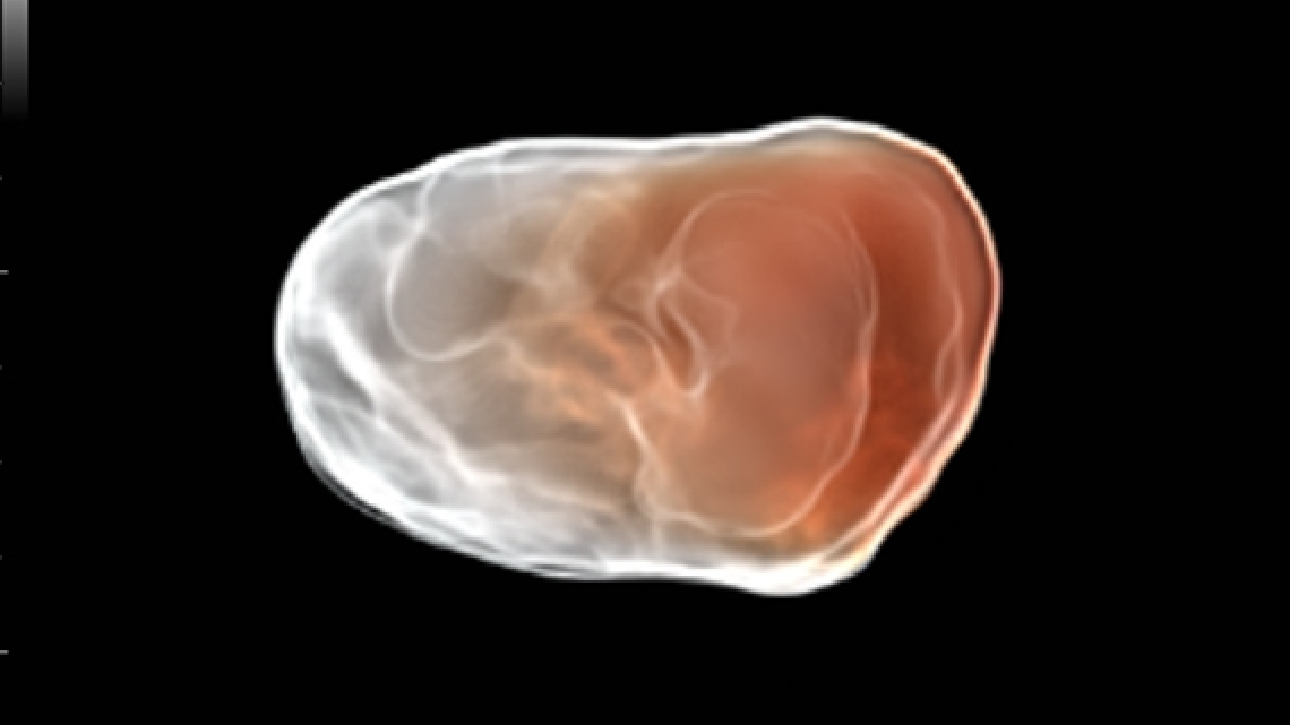

Imagens clĂnicas